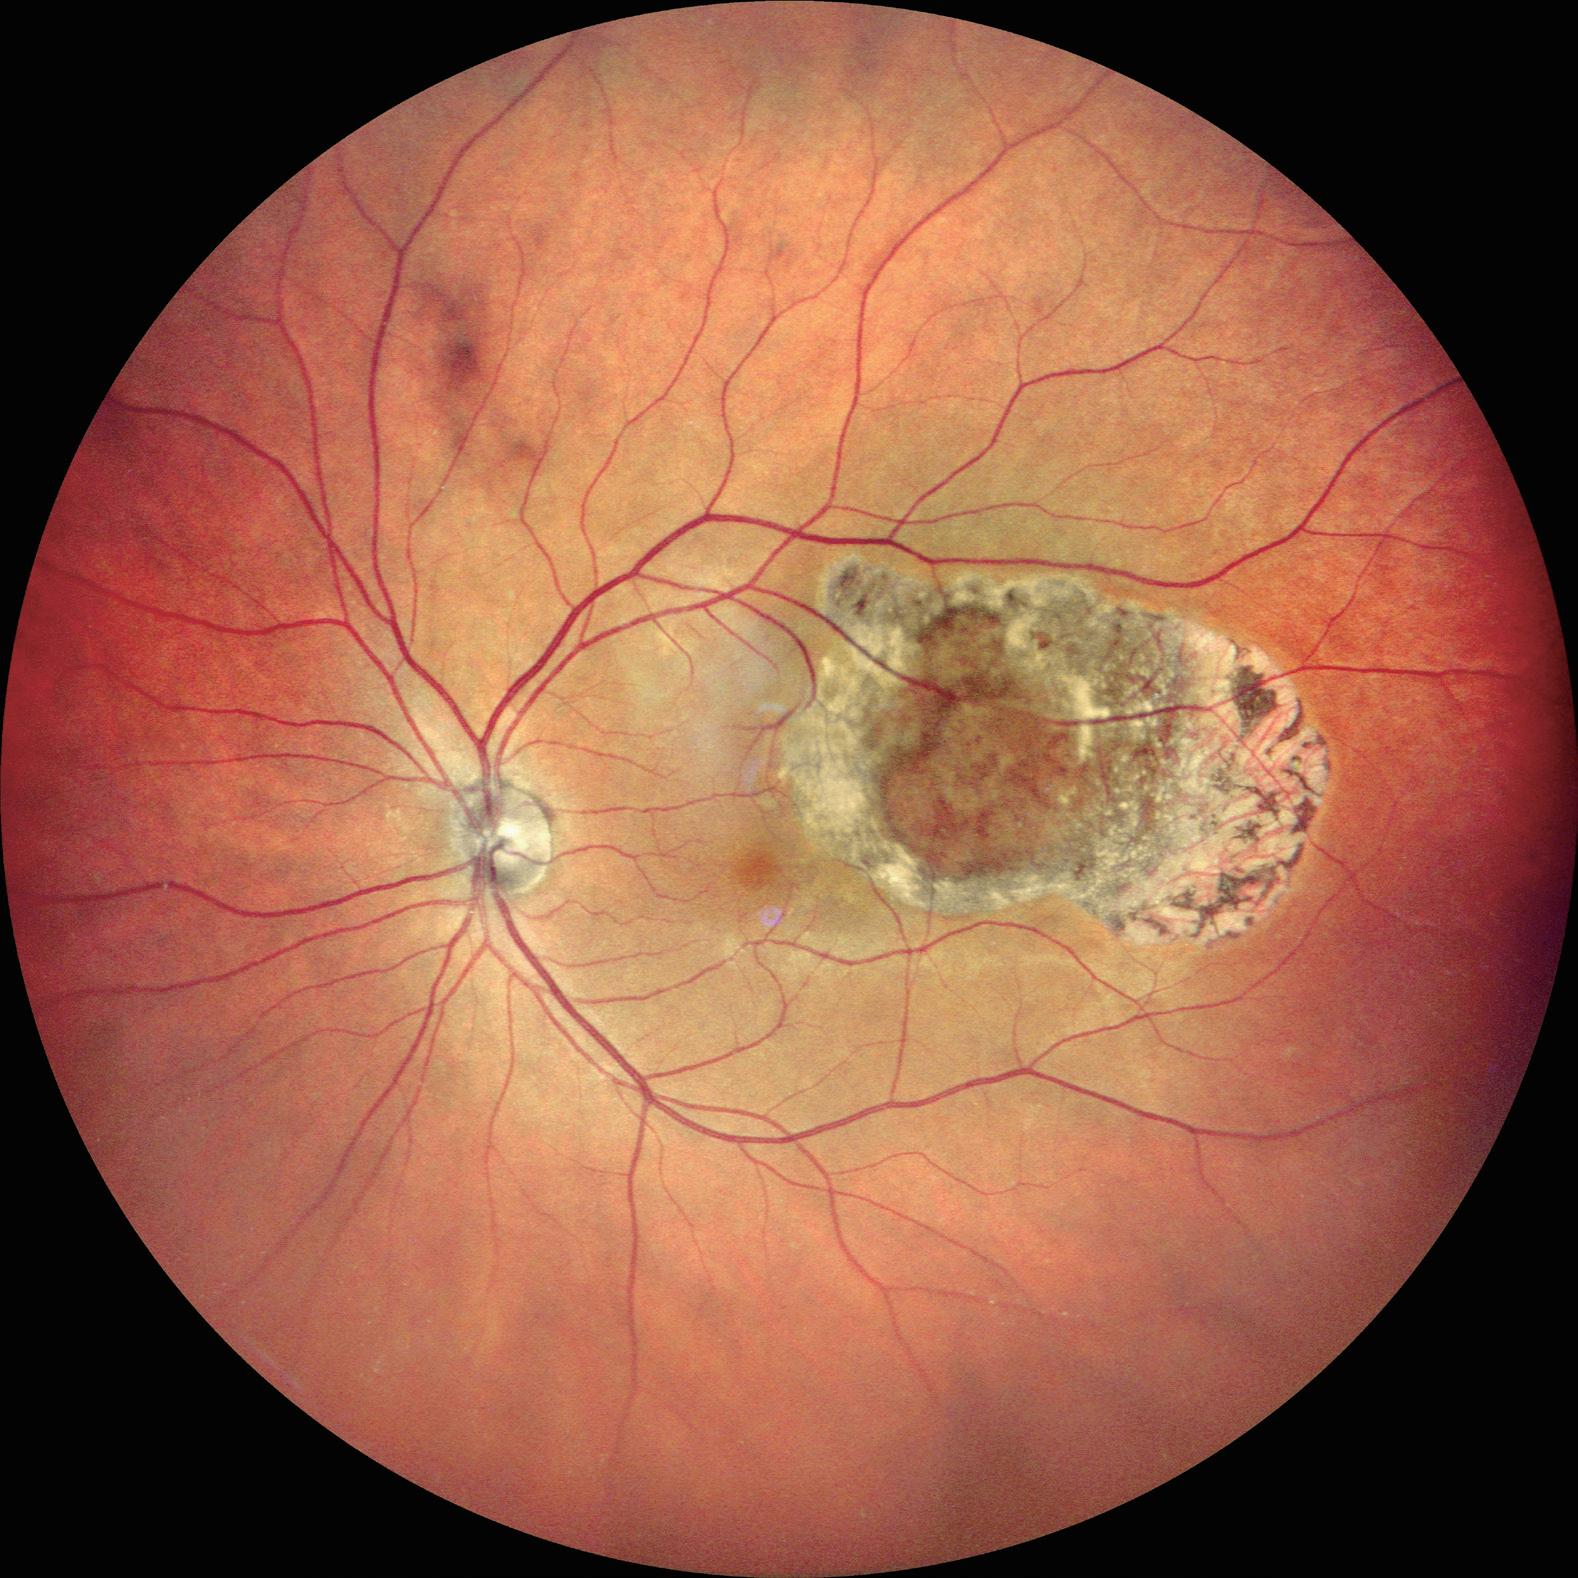

28 Gene Therapy for X-Linked Retinitis Pigmentosa

Robert MacLaren MD, PhD

29 Preserving Foveal Function in Geographic Atrophy

Usha Chakravarthy MD, PhD